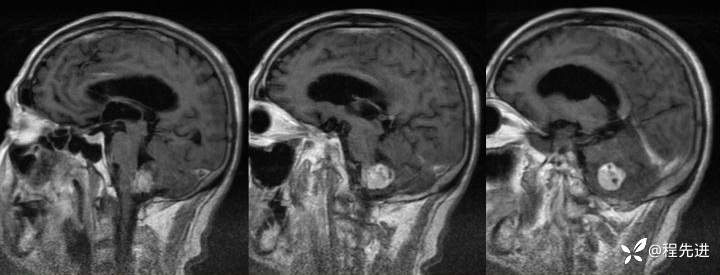

【患者信息】:男,66岁

【现病史及既往史】:头痛半年,行走不稳3个月

增强:

img